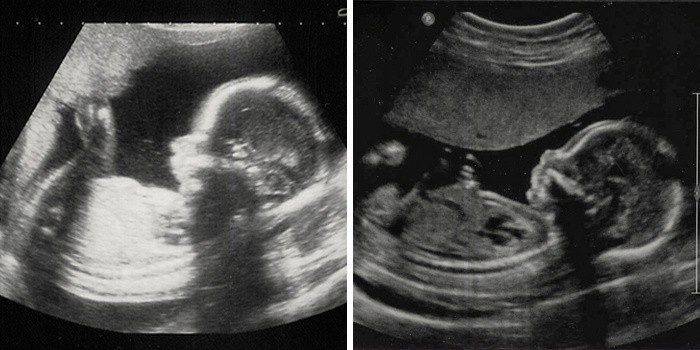

Фотография Плода В Животе

Фотография Плода В Животе 113 фотографий